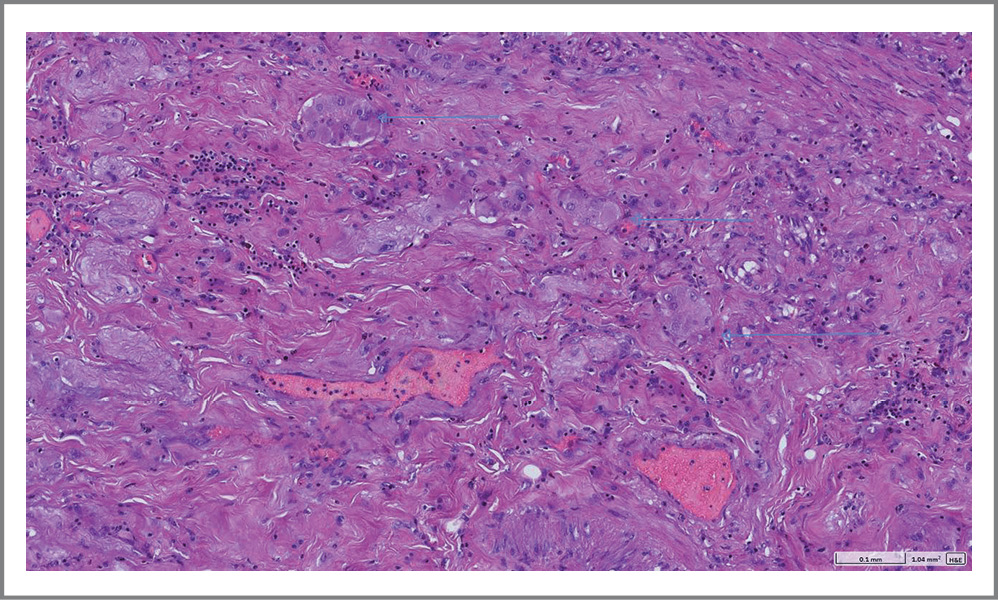

Проведено микроскопическое исследование операционного препарата. Обнаружены фрагменты стенки ТК с язвенным дефектом глубиной до подслизистой основы, занимающим около 50% окружности СО. Дно дефекта представлено фиброзно-склеротической тканью со зрелой грануляционной тканью, наложениями фибрина и гранулоцитов по поверхности. СО в краях дефекта с очагами псевдопилорической метаплазии. Артерии и артериолы в дне дефекта с очагами гиалиноза. Мышечный слой стенки и серозная оболочка типичного морфологического строения. В жировой клетчатке брыжейки обнаружен лимфоузел с реактивными изменениями.

Заключение. Микроскопическая картина характерна для хронической язвы ТК с активным воспалением, началом формирования фиброзной стриктуры (рис. 5–8).

Рис. 6. Микроскопические изменения в стенке резецированной ТК. Фиброзно-склеротические изменения распространяются сквозь мышечный слой в субсерозный (признак формирования стриктуры).

Fig. 6. Microscopic changes in the wall of the resected jejunum. Fibrosclerotic changes extend through the muscle layer into the subserosa (a sign of stricture formation).

Рис. 8. Микроскопические изменения в стенке резецированной ТК. Гиперплазия стволиков нервного (Мейсснерова) сплетения подслизистой основы ТК (встречается в дне хронических язвенных дефектов).

Fig. 8. Microscopic changes in the wall of the resected jejunum. Hyperplasia of the trunks of the Meissner's plexus of the submucous layer of the jejunum (observed in the bottom of chronic ulcerative defects).